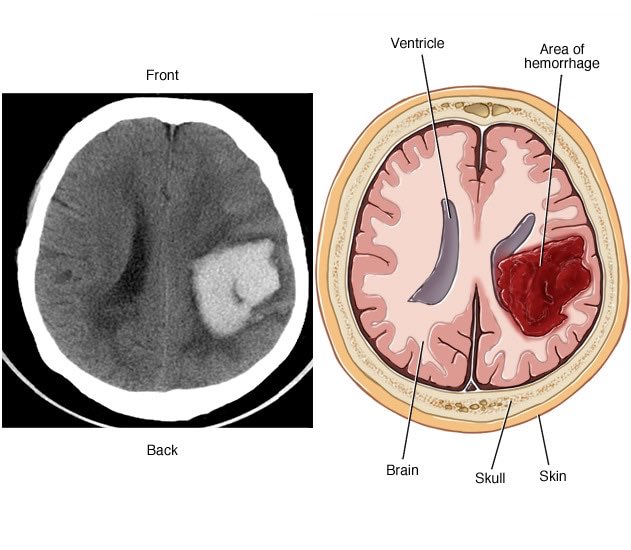

🔴 IntraCerebral or cerebral hemorrhage

النزيف هنا يصير في فصوص الدماغ أو المخيخ وأي مكان آخر داخل الدماغ نفسه

🔴 IntraVentricular hemorrhage

وهنا يصير النزيف في بطين (تجاويف) الدماغ